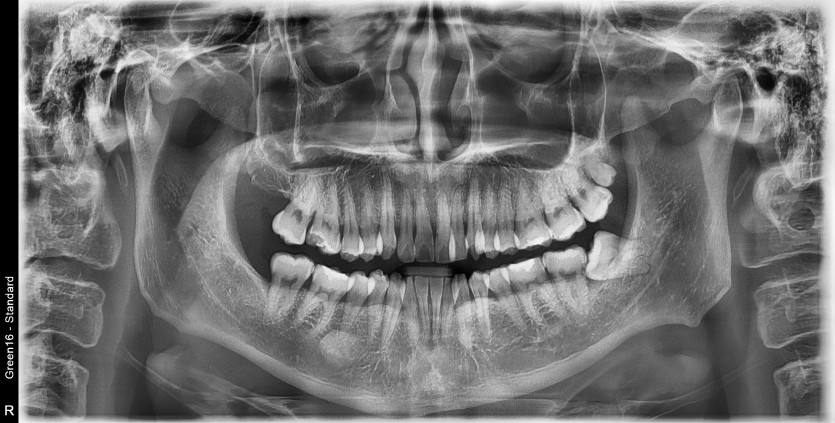

#28,38 사랑니 발치

구강 외과 전문의가 당일 발치했습니다.